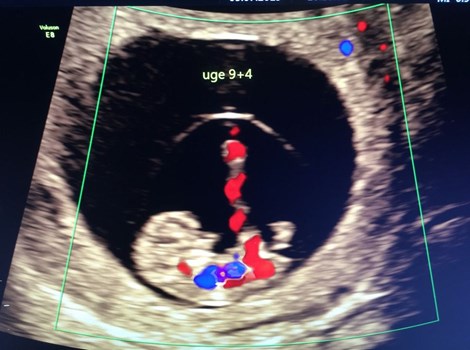

Se hele opslaget på Herning Løve Apotek v/Henrik Krog Jensens FacebooksideTIDLIG SCANNING - hvorfor er det en god idé ? En tidlig scanning giver jer først og fremmest vished om graviditeten. Er det lille liv kommet godt igang ? Venter vi kun ét barn ? Og derefter nok det v...

Se hele opslaget på Hjertelyd - scanningsklinik for gravides Facebookside